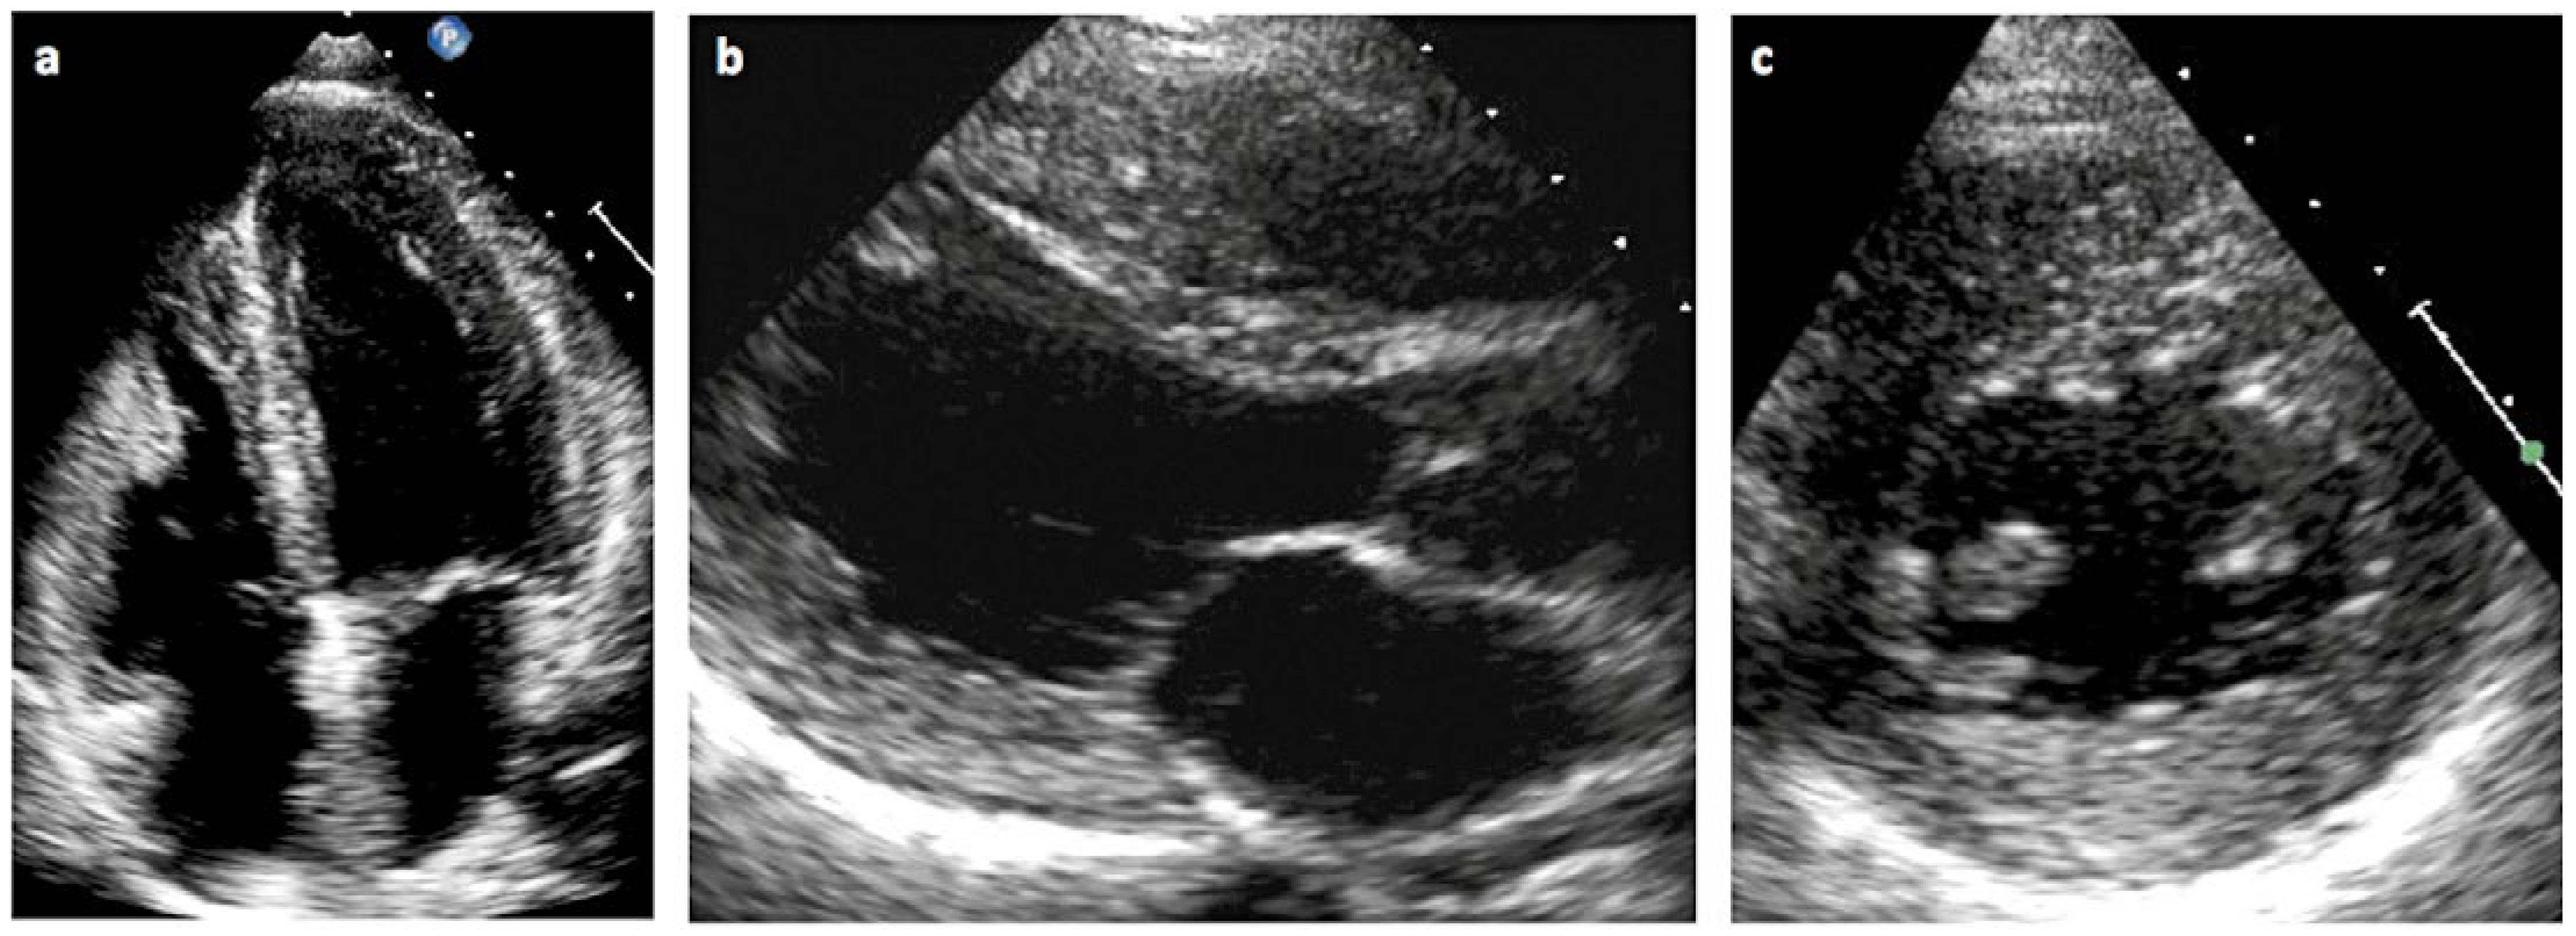

- Charakteristische EKG-Veränderungen und/oder echokardiografische veränderungen im Sinne einer linksventrikulären Hypertrophie können Manifestationen eines Morbus Fabry sein.